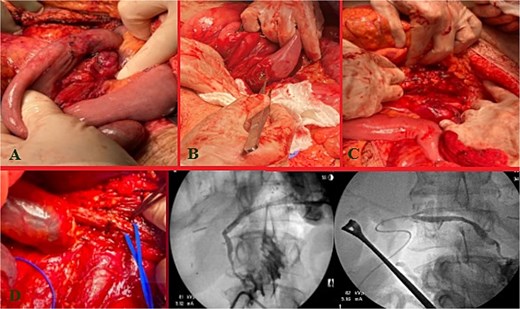

Massive transfusion protocol was initiated, and he was taken to the operating room for an emergent exploratory celiotomy. Upon entrance into the abdominal cavity, a 10 cm hematoma, along the transverse colon consistent with a mesenteric arterial hemorrhage, was identified and rapidly controlled (Fig. 1A). A Cattell-Braasch maneuver was employed, mobilizing the right colon, and a Kocher maneuver to fully explore the duodenum, revealing a AAST Grade II D2 injury that was repaired in 2 layers (Fig. 1B). The pancreatic head and tail had AAST Grade II injuries with multiple arterial bleeds that were controlled with suture ligation and argon beam coagulation (Fig. 1C).

Index operation. A: Transverse colon hematoma. B: Duodenal (D2) injury. C: Pancreatic head and tail vascular injury. D: Common bile duct and intraoperative cholangiogram through the common bile duct and cystic duct.

On initial inspection, the GB infundibulum was contused, and there was bile staining along the porta hepatis. The common bile duct (CBD) was identified and appeared grossly normal. However, due to the proximity of the pancreatic head injury and bile staining, we performed an intraoperative cholangiogram (IOC) through a mid-portion CBD needle ductotomy, to spare the GB as a potential conduit if a biliary repair was required. The initial IOC did not reveal an injury to the CBD and did not demonstrate extravasation of contrast (Fig. 1D). The needle ductotomy was closed with a running 3–0 Monocryl stitch. As we were concluding the damage control laparotomy a persistent, mild, bile staining within and along the porta hepatis, was noted. The possibility of a more proximal extrahepatic bile duct injury was raised as the common bile needle ductotomy closure remained intact.

Further inspection of the GB and proximal extra biliary ductal system revealed a large GB bed hematoma and partial avulsion of the GB (AAST Grade 3). Due to the risk of delayed GB ischemia, a cholecystectomy, and an additional IOC via the cystic duct this time was performed to rule out a more proximal ductal injury and a possible bile leak from the prior IOC distal needle ductotomy. The more proximal and distal IOC did not reveal a bile leak, however, the more proximal ductal structures were not optimally demonstrated. No further bile staining was noted. The abdomen was irrigated, and 4 Jackson-Pratt (JP) drains and an AbThera™ Advance Open Abdomen Dressing (3 M, Saint Paul, MN, USA) were placed. The patient was stabilized and transferred to the intensive care unit (ICU) for further resuscitation, on triple antibiotics, pantoprazole, and a somatostatin drip.